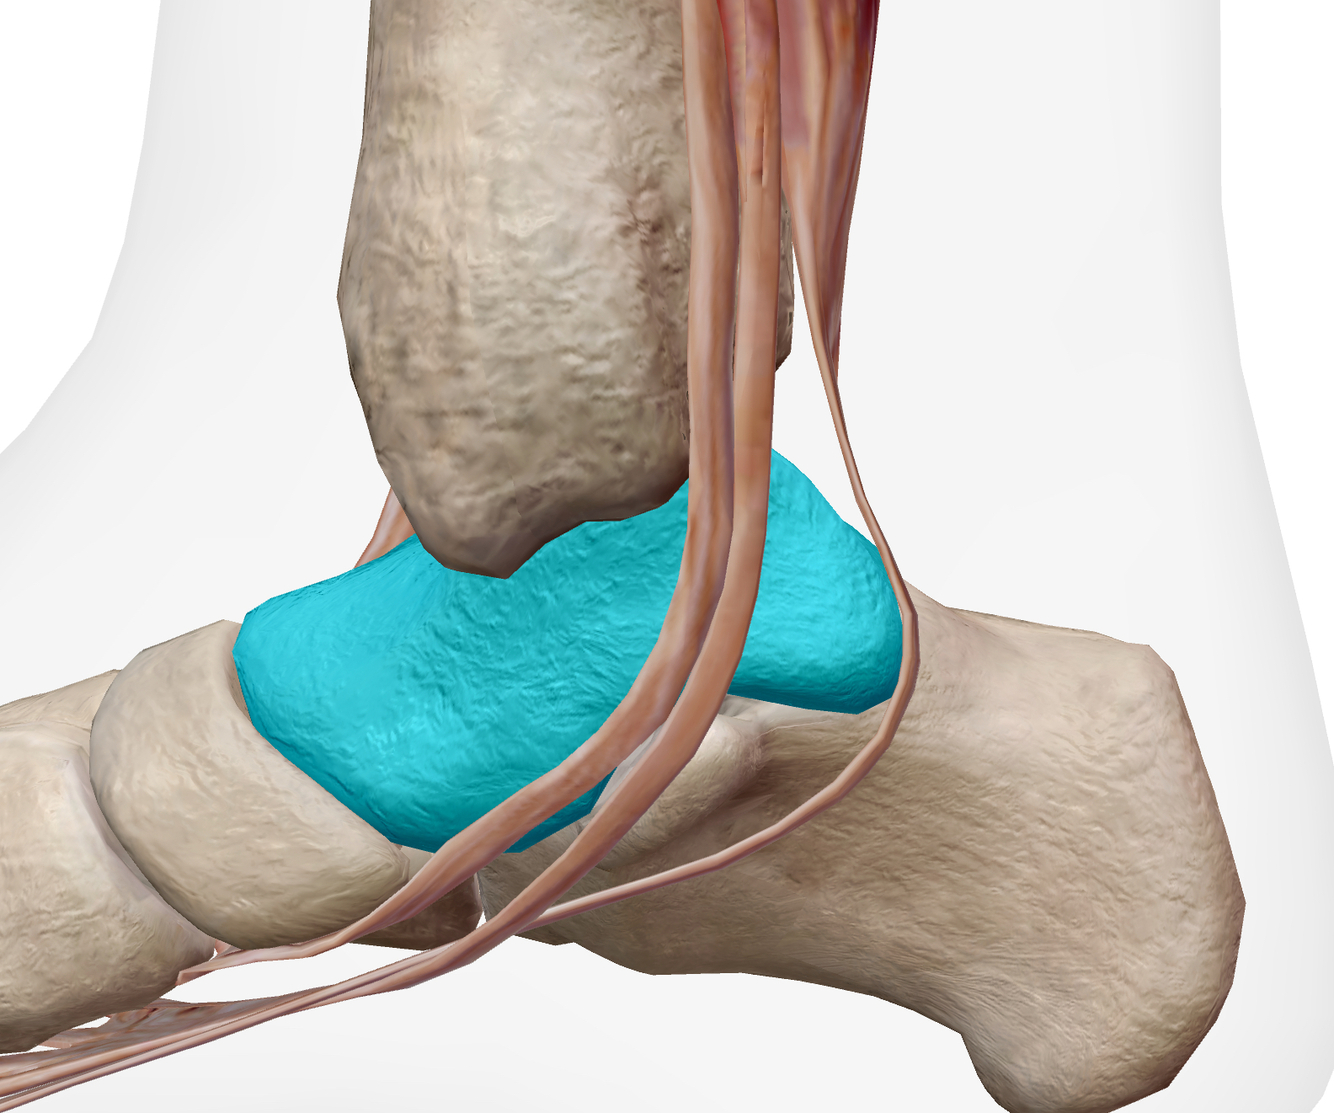

Identifier les structures sur cette image.

Indice: On y voit les os suivants : Tibia, talus et calcanéus

A